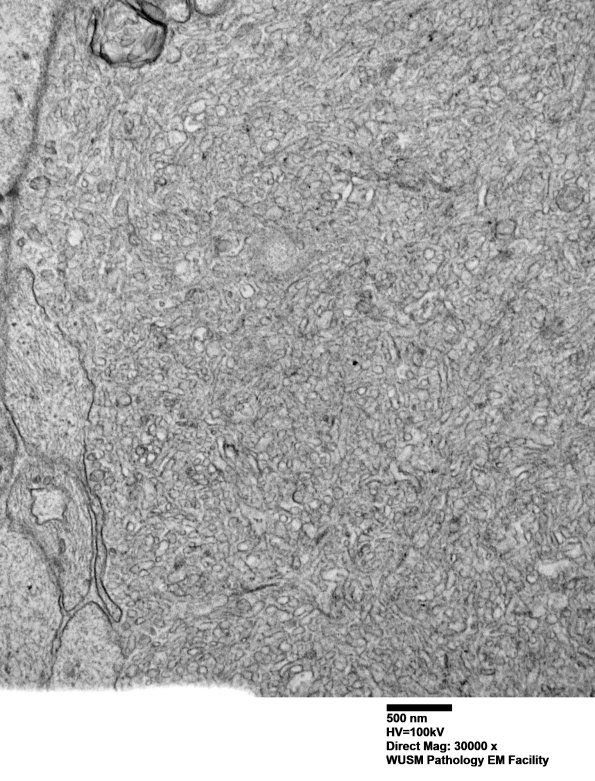

Higher magnification of image #16C1. (electron micrograph)